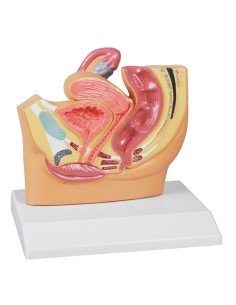

3B Modèle scientifique et gynécologique pour l'entretien avec les patientes P53

3B Scientific. Kit d'enseignement, système de reproduction femelle W40214